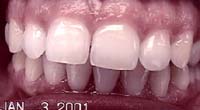

Treatment Time: 6 months

Aligners: 12 Upper, 7 Lower